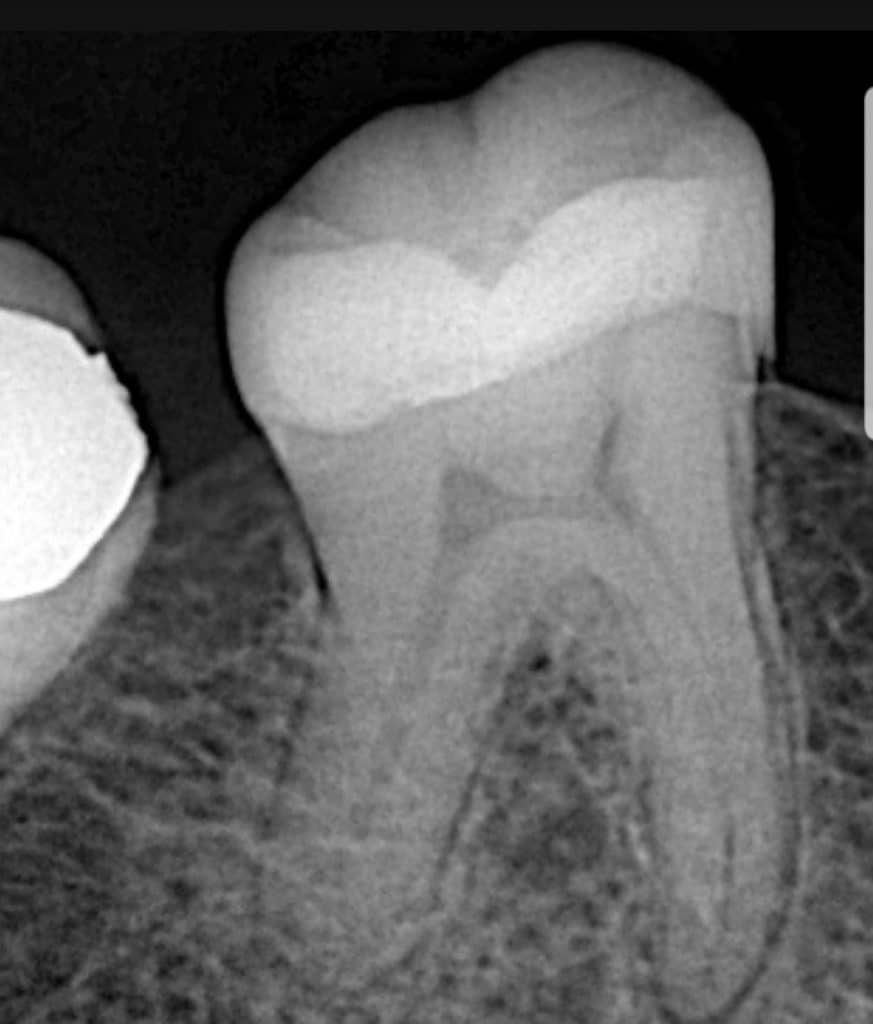

Post operative X ray